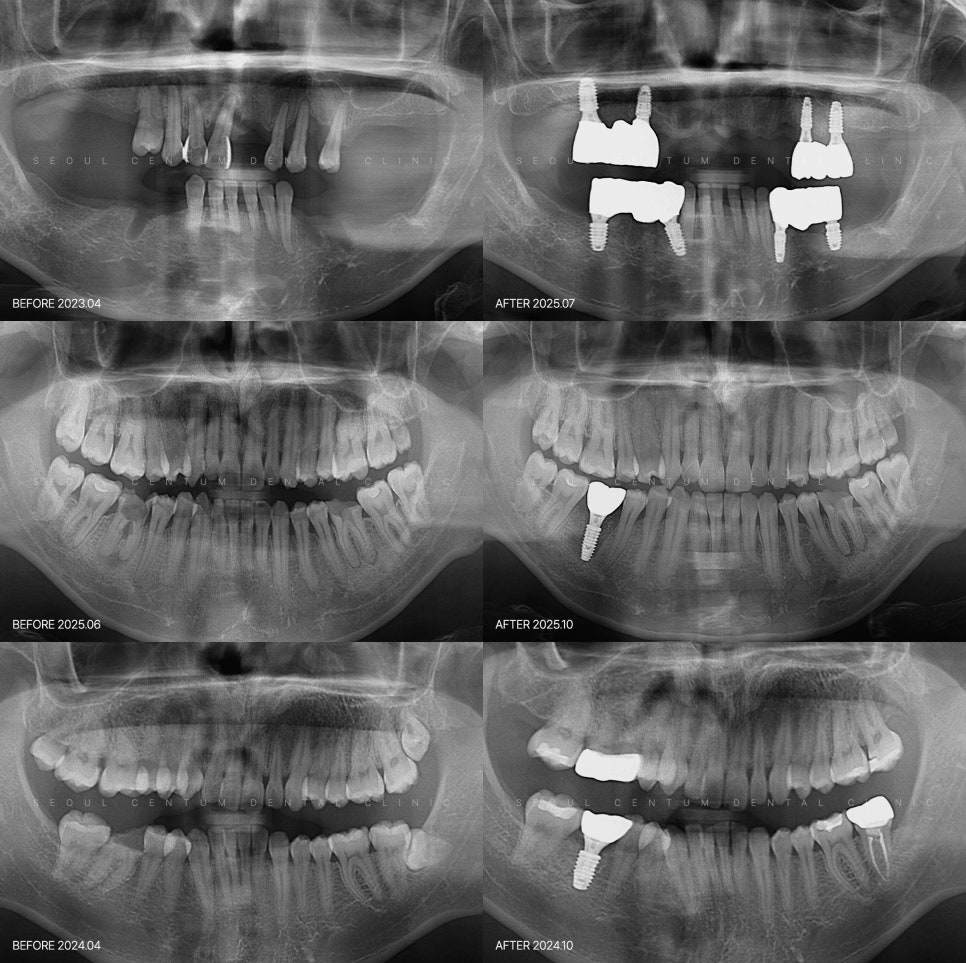

파노라마 엑스레이와 3D CT 등의

장비를 활용한 정밀 진단이 가능한지,